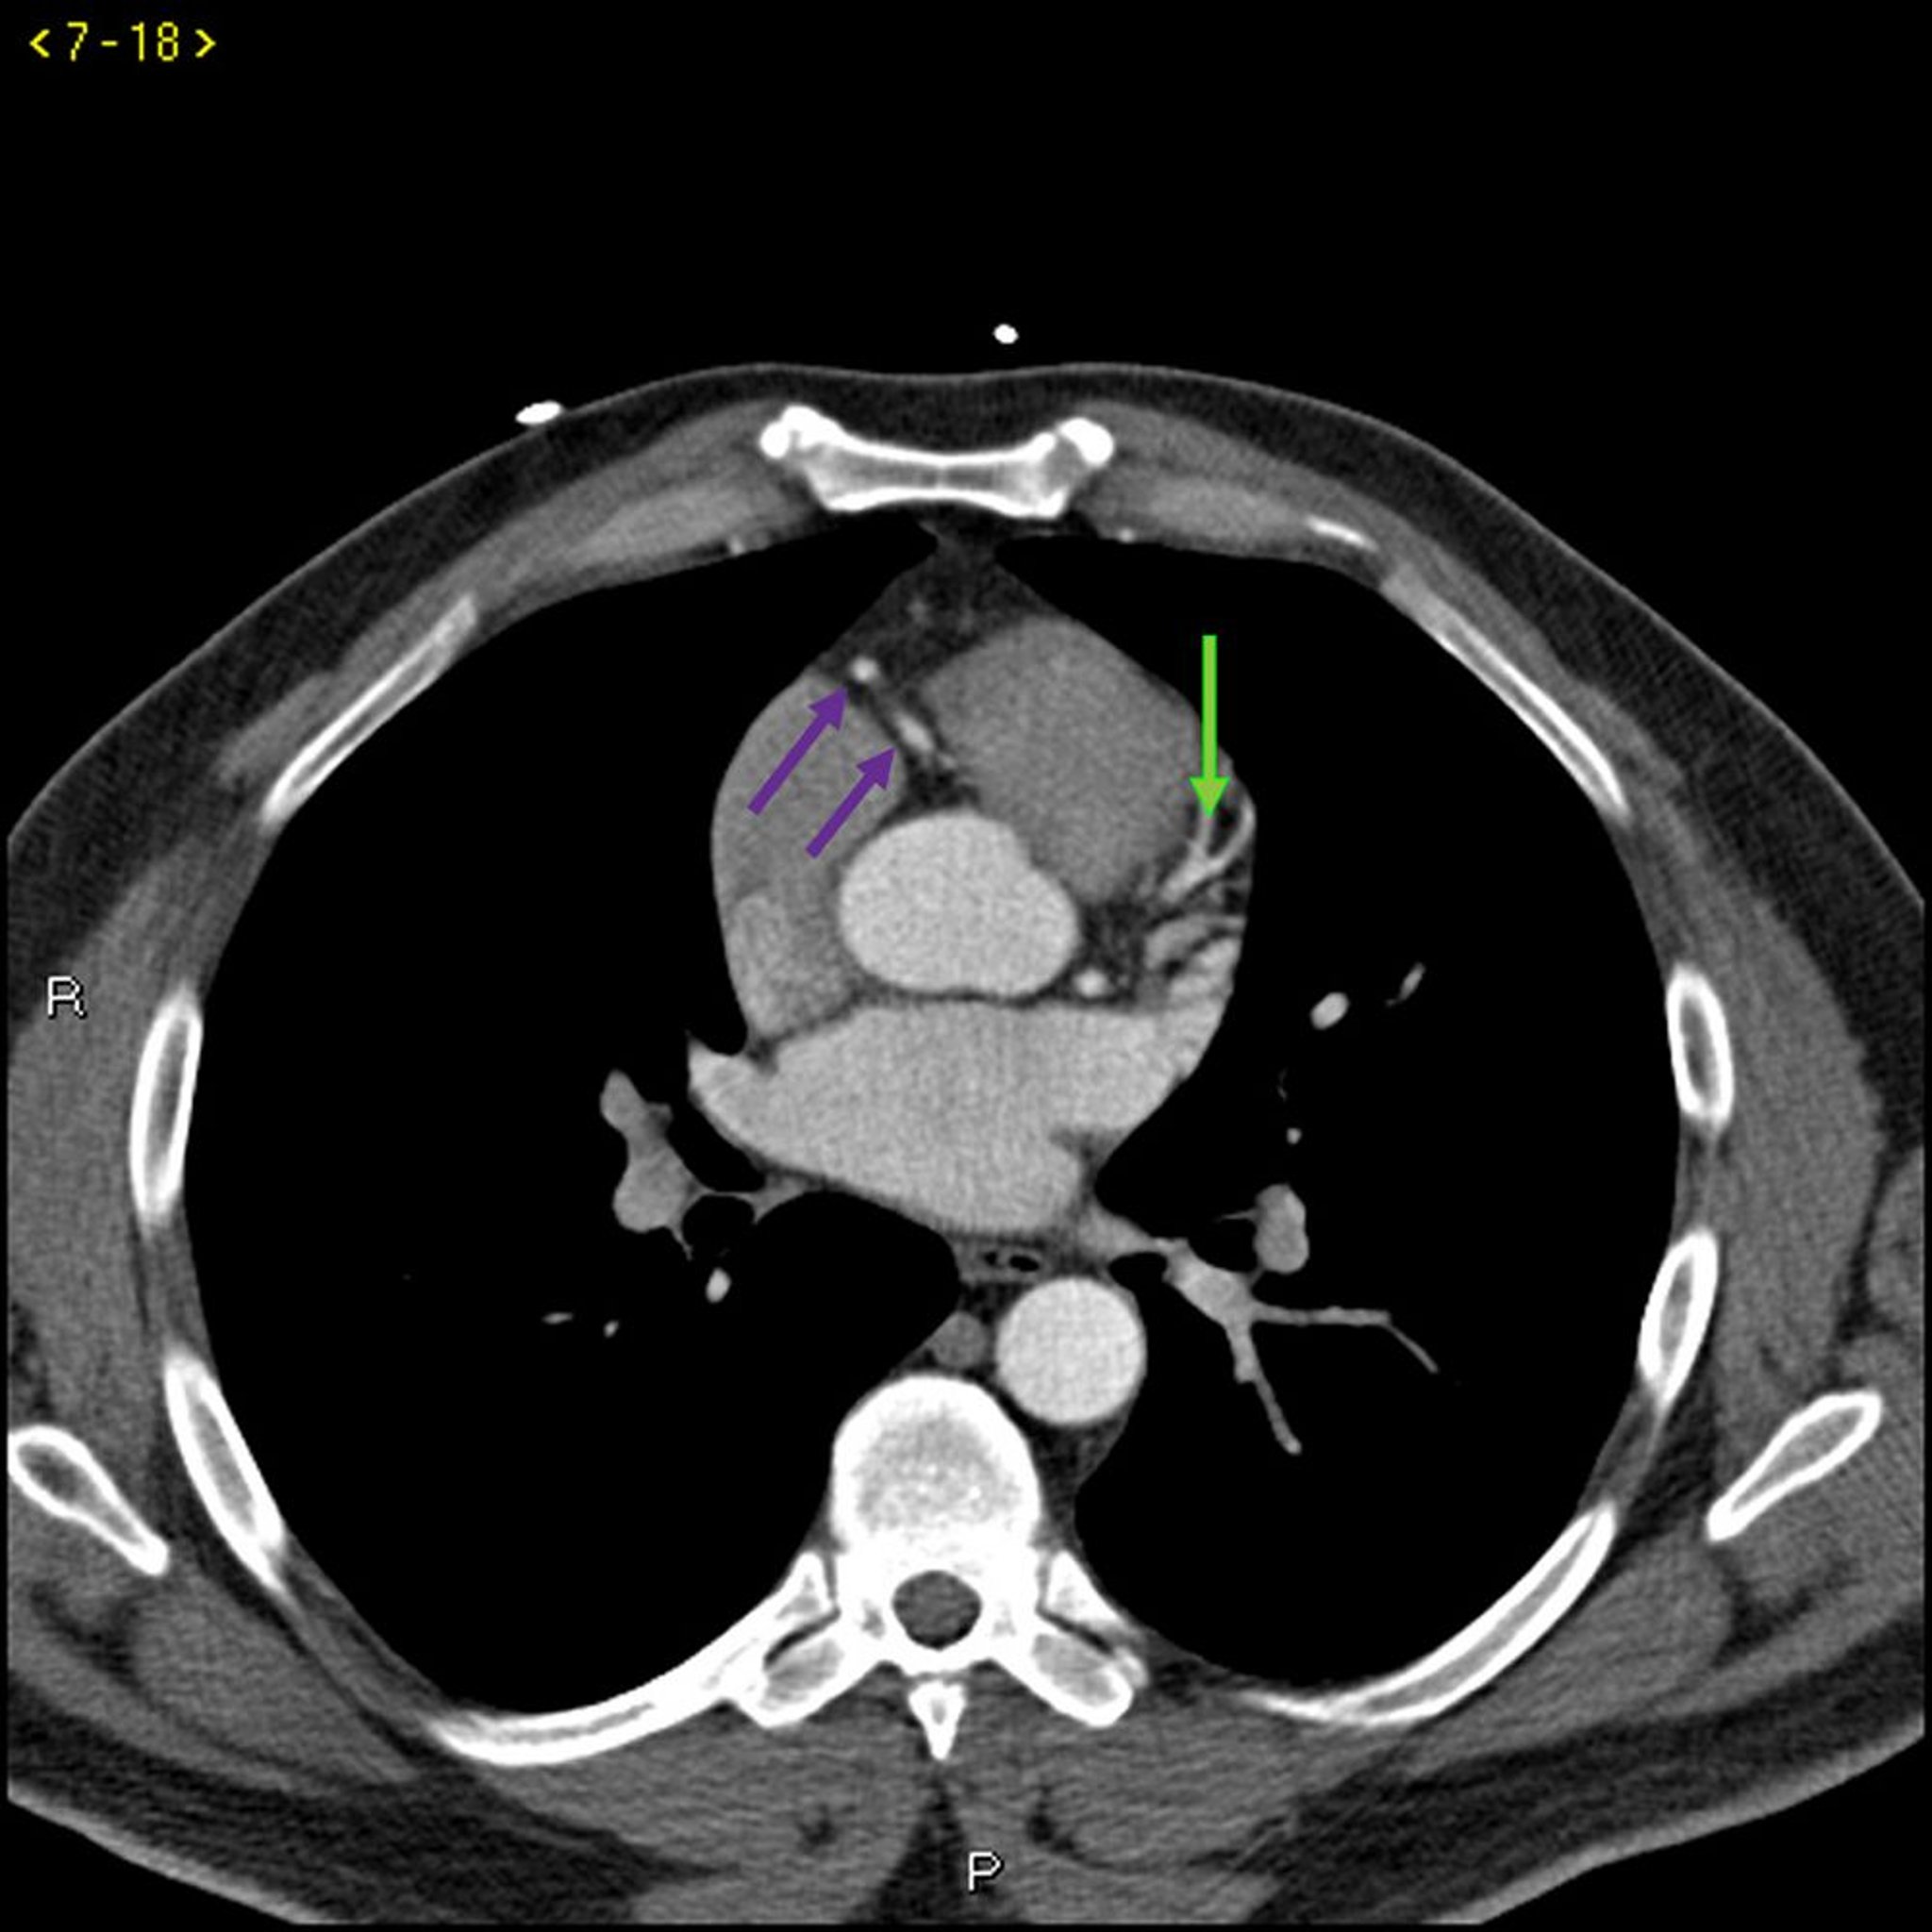

Tomografía computarizada con contraste que muestra arterias coronarias normales–diapositiva 3

Esta TC con contraste muestra arterias coronarias normales. La arteria principal izquierda está indicada por la flecha roja. Las arterias descendente anterior izquierda y circunfleja izquierda están indicadas por las flechas verde y azul respectivamente, y la arteria coronaria derecha está indicada por la flecha púrpura.